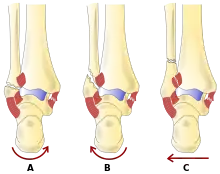

La région de la cheville fait référence à l'endroit où la jambe rencontre le pied (région talocrurale)[4]. L'articulation de la cheville est une articulation charnière complexe et fortement contrainte composée de trois os : le tibia, le péroné et le talus[5],[6]. L'aspect porteur du tibia le plus proche du pied (appelé plafond) se connecte avec le talus. Cette articulation (où deux os se rencontrent) est principalement responsable de la flexion plantaire (déplacer le pied vers le bas) et de la dorsiflexion (déplacer le pied vers le haut)[6]. Ensembles, le tibia et le péroné forment une douille en forme de support connue sous le nom de mortaise, dans laquelle s'insère le talus en forme de dôme[7]. Le talus et le péroné sont reliés par un groupe solide de ligaments, qui soutiennent la face latérale de la cheville. Ces ligaments comprennent le ligament talo-fibulaire antérieur (ATFL) et le ligament talo-fibulaire postérieur (PTFL)[8]. Le ligament calcanéo-fibulaire (LFC), qui relie le péroné au calcanéum, ou os du talon, fournit également un soutien latéral. Le ligament deltoïde soutient la partie médiale de la cheville (la plus proche de la ligne médiane). Il empêche le pied de s'éverser excessivement ou de se tourner vers l'extérieur, tout en empêchant également le talus de tourner vers l'extérieur[8]. Les parties distales du tibia et du péroné sont reliées par un réseau de tissu conjonctif appelé syndesmose, composée de quatre ligaments et de la membrane interosseuse[8].

- La classification de Lauge-Hansen (en) classe les fractures selon le mécanisme de la blessure en fonction de la position du pied et de la force de déformation (le type le plus courant est la supination-rotation externe).

- La classification Danis-Weber (en) classe les fractures de la cheville selon le niveau de la fracture de la fibula distale (type A = en dessous du ligament syndesmotique, type B = à son niveau, type C = au-dessus du ligament), avec une utilisation dans l'évaluation des lésions de la syndesmose et la membrane interosseuse.